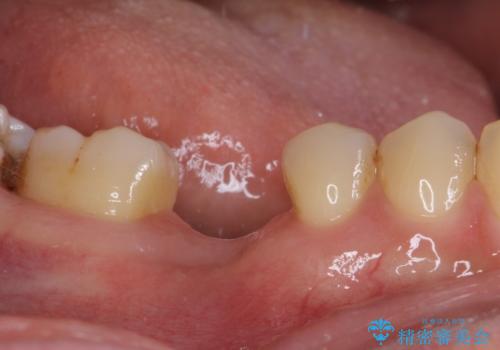

- 大学病院でインプラント治療を進めていたものの、予約のタイミングが合わないとのことで来院された患者様です。

欠損部位の骨や歯肉の状態は非常に良く、速やかにインプラント埋入を行い、補綴治療を進めて行くことのできる状態でした。

当院の予約も空きはあまりないのですが、キャンセルが出たタイミングなどをうまく活用し、速やかに進めて行くこととしました。